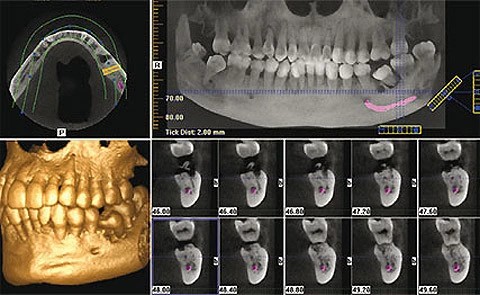

Your journey starts with an in-depth consultation, including advanced imaging, to evaluate your oral health and determine if you need bone grafting or a sinus lift.